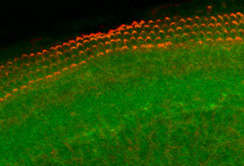

An dem Projekt „Nanoear“ haben insgesamt 14 Universitäten und zehn Firmen aus elf verschiedenen Ländern gearbeitet. Koordiniert wurde die Forschungsarbeit von der Universität Tampere in Finnland. Das von der EU finanzierte Projekt hatte ein Volumen von 10,5 Millionen Euro. Vom Forschungslabor für Innenohrbiologie in Innsbruck waren Dr. Rudolf Glückert, Mag. Christian Pritz, Dr. József Dudás, Dr. Soumen Roy und BMA Mario Bitsche unter der Leitung von Prof.in Schrott-Fischer an dem Projekt beteiligt. „Unser Beitrag war vor allem die Entwicklung eines Invitro-Modells, mit dem die entwickelten Nanopartikel an Zellen und Organkulturen getestet werden konnten“, sagt die Teamleiterin. Dadurch konnte die Auswirkung der Partikel auf das lebende Gewebe erforscht werden.